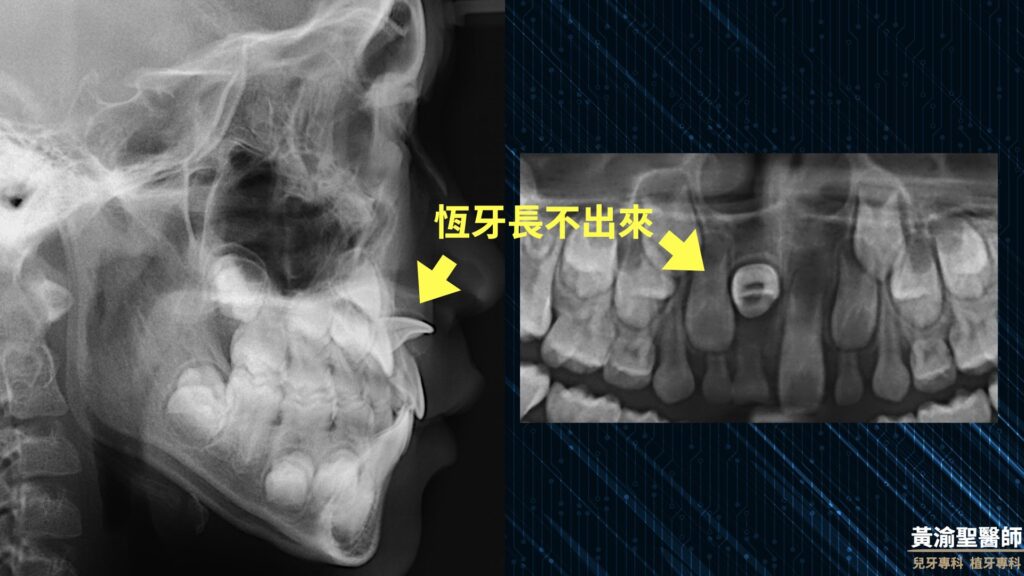

0 評論 0 FacebookTwitterTelegramLINEEmail 自上次分享前牙阻生的知識後 小黃醫師門診突然多了好多前牙有狀況的孩子 這次小黃醫師用一個臨床案例與您分享 如何治療前牙阻生 小陳年方8歲 曾有乳牙撞傷歷史 由圖可見前牙發黑 牙齒遲遲不掉 媽媽很擔心 有受傷歷史且對稱牙齒已長超過半年 這時候小黃醫師心中的警鈴已經叮叮想起 腦中浮現抖音神曲叮叮噹噹 接著就跳了起來 這首歌很洗腦 從各式影像檢查就可以發現 門牙很有個性的往前長 這樣的狀況當然需要介入治療 趕快先拔掉變色的乳牙 觀察3個月 發現恆牙並沒有改善位置 進入矯正治療 首先黏上矯正器讓每顆牙齒乖乖站好 幫阻生門牙留下足夠的空間 接著就辛苦小陳了 小黃醫師會開個小小的刀 恩就算很難 也會跟小朋友說小小的刀 (不過跟植牙牙周手術相比, 阻生齒手術真的簡單很多) 幫阻生門牙黏上一顆矯正器 慢慢的有耐心的拉出來 最後終於還給小陳帥氣的微笑 如果您對於孩子是否有前牙阻生感到擔心 不妨參考小黃醫師上一篇文章歐 門齒阻生-門牙長不出來 多數情況及早發現 都能得到很好的治療結果 定期檢查超重要 每次少少的掛號費 就是避免大問題突然出現 讓孩子經歷莫大的辛苦 謝謝您的觀看 也歡迎分享給小孩正在就讀小一的朋友歐 #黃渝聖醫師 #一分鐘小常識 #不看字就看圖 #兒童牙科 #美容牙科 #口腔衛教 #植牙專科 #兒牙專科 #家庭牙科專科 #員林基督教醫院 #彰化基督教醫院 #兒童早期矯正 #MRC #肌功能訓練 返回首頁 MRC一分鐘小常識不看字就看圖兒牙專科兒童早期矯正兒童牙科口腔衛教員林基督教醫院家庭牙科專科彰化基督教醫院植牙專科美容牙科肌功能訓練門牙阻生門齒阻生黃渝聖醫師 0 評論 0 FacebookTwitterTelegramLINEEmail 上一篇 門齒阻生-門牙長不出來🥺 下一篇 小兒常見牙科藥物與蠶豆症 你可能也會喜歡 兒童早期矯正-努力才能讓你的... 牙齒的溜滑梯-咬合斜坡 全口蛀牙重建-睡覺治療 醒來你... 陶瓷嵌體-保留齒質的好方法 乳牙小鋼牙 兒童早期矯正 前牙錯咬 地包天-前牙錯咬 早期矯正治療 矯正會不會「超級痛」? 前牙逆向錯咬 牙齦萎縮 兒童早期矯正 前牙錯咬